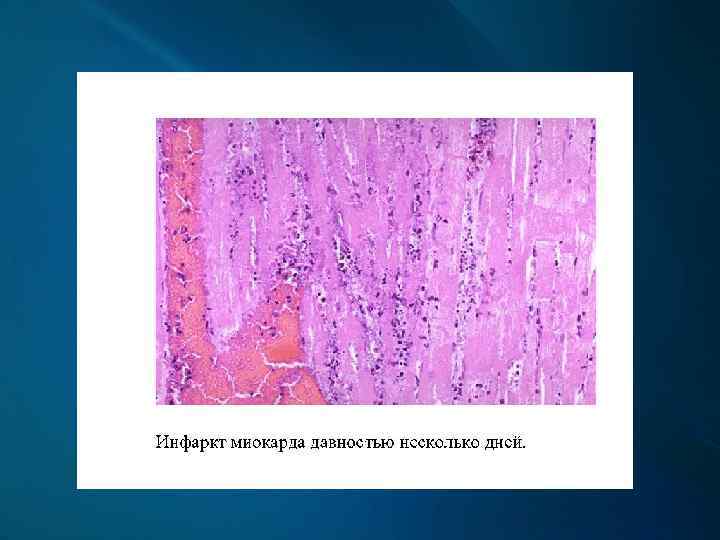

Макроскопически: первые часы - миокард дряблый, неравномерно кровенаполнен; через 18 -24 ч. – четко виден некроз; конец 1 -х сут. – некроз глинистокрасноватый, выбухает из-за отека, с геморрагическим венчиком; к 4 -6 сут. и далее – некроз западает, плотный, желто-серый, с красной каймой грануляционной ткани вокруг; через 3 -5 нед. – рубец красновато-серый, затем белесовато-серый.